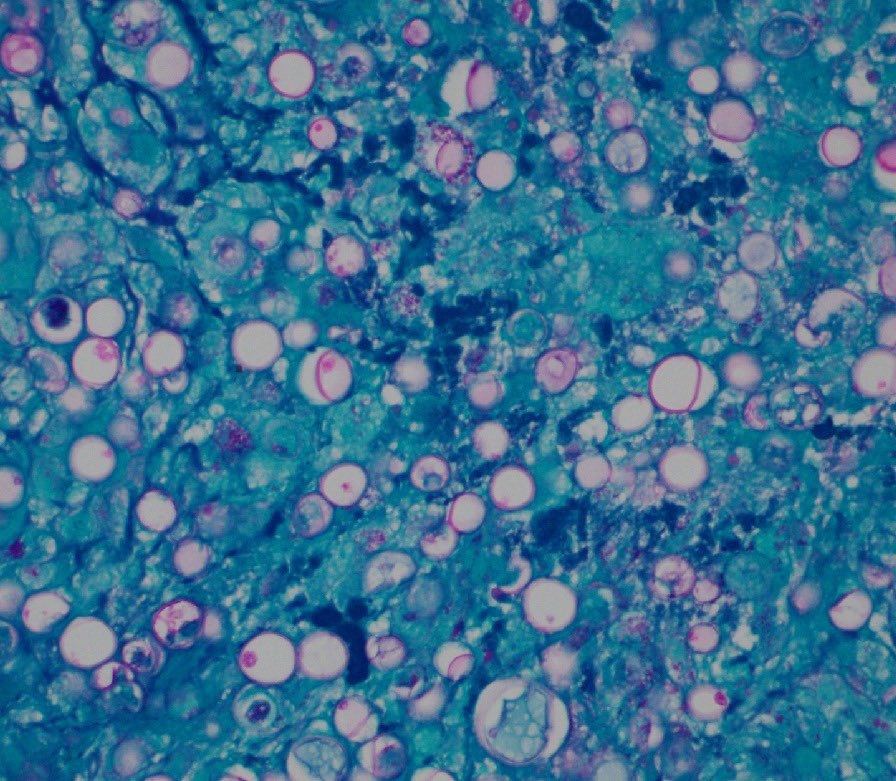

"BOW TIE". Papillary thyroid carcinoma. #FNA Thyroid. #Entpath #endopath #pathology #pathtwitter #PathTweetAward @MSWPathology @MyCytopathology @SamKhader